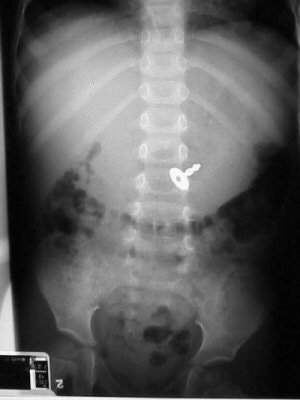

![]() |

| Figure 12 |

Figure 12 shows an eight-year-old girl who has swallowed her diary key. I sat her on my knee and asked her what would happen the next time she had to write in the diary. Her quizzical expression and that inevitable look of realization were priceless.